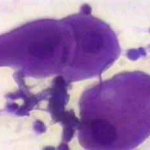

Πινακοθήκη κυτταρολογικών ευρημάτων ΙΙΙ

Οι πινακοθήκες κυτταρολογικών ευρημάτων, έχουν σαν στόχο να εμπλουτίσουν την κυτταρολογική εμπειρία σπουδαστών και ειδικευομένων, όπως ένας άτλαντας.

Παρουησιάζονται λοιπόν τυχαία ευρήματα, από το καθημερινό γυναικολογικό ιατρείο.